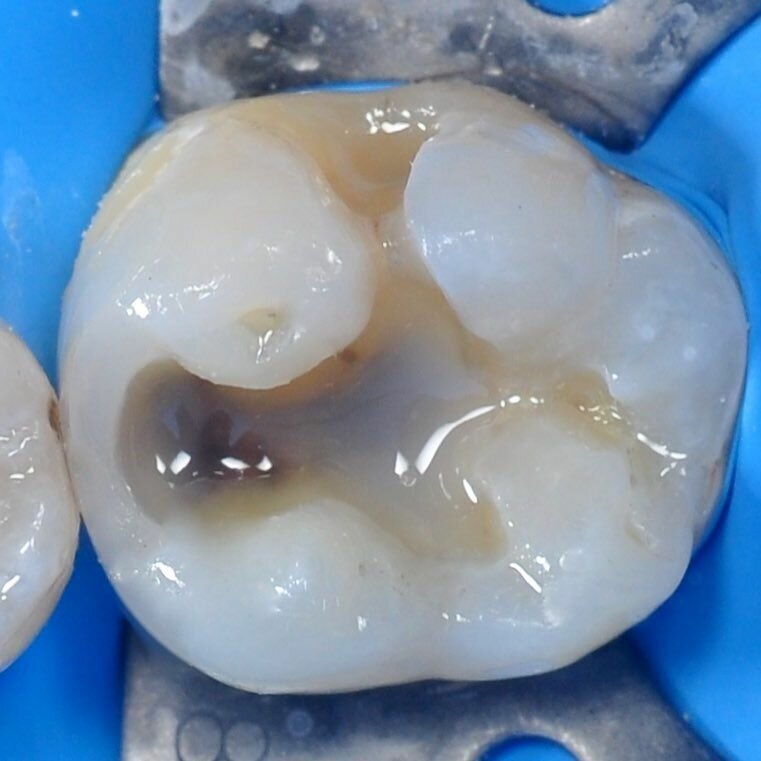

Начну с того,что кариес это- сложный, медленно текущий патологический процесс, протекающий в твёрдых тканях зуба и развивающийся в результате комплексного воздействия неблагоприятных внешних и внутренних факторов. При его возникновении повреждается сначала зубная эмаль, а затем, если не начать лечение, и дентин (твердая ткань зуба). Первый признак кариеса — темное пятно на эмали. Если игнорировать его появление, то пятно может увеличиться в диаметре, а затем патология распространяется глубже в ткань зуба, в результате чего образуется «дырка».

На этой фотографии можно заметить все стадии развития кариеса. Развивается в результате комплексного воздействия неблагоприятных внешних и внутренних факторов. В начальной стадии развития кариес характеризуется очаговой деминерализацией неорганической части эмали и разрушением её органического матрикса. Особенно часто кариес развивается когда у человека недостаточно витаминов,например:когда человек мало ест творога,мяса,фруктов и овощей.

Кариес ранней стадии можно увидеть по цвету эмали или пятна(светлого или тёмного)Причины появления кариеса таковы:бактерии, которые вырабатывают кислоты, вымывающие фтор и кальций из ткани зуба. Микроорганизмы начинают размножаться и разрушать зуб уже через 1–2 часа после чистки полости рта, приводя к образованию зубного налета. Недостаточное слюноотделение тоже может способствовать развитию кариеса. Дело в том, что минеральные вещества слюны способны частично нейтрализовать вырабатываемые бактериями кислоты — когда слюны образуется мало, кислоты быстрее разрушают зубы. Также слюна частично смывает налет.